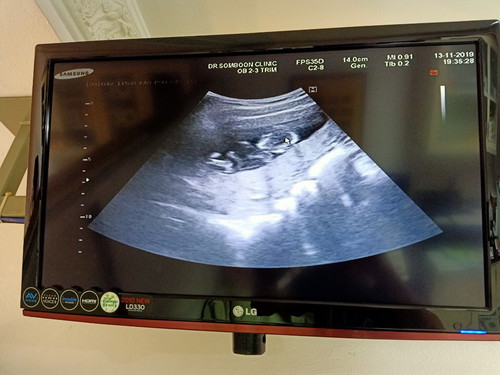

หนูดั้งโด่งนะค้าาา หมอบอก #18W4D

บ้านนี้รู้สึกชัด20วีคค่ะ รูปนี้ซาวด์ตอน5เดือนโด่งมาก คลอดมาแก้มดึงดั้งไปหมดเลยค่ะ😂😂

ไปซาวด์ที่ไหนกันค่ะได้ภาพชัดขนาดนี้คลินิครึเปล่าบ้านนี้ซาวด์รพ.ดูแทบไม่ออกเลยจ้า

คลินิคจ้า